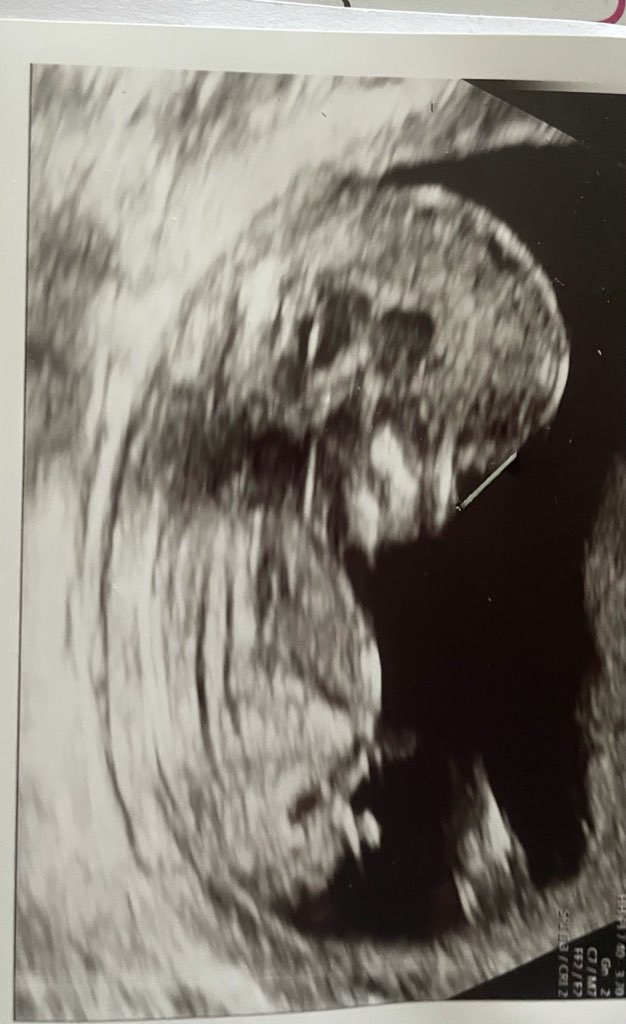

Hej dziewczyny, dzisiaj pierwsze prenetalne, 13+6, lekarz powiedział że to prawdopodobnie chłopiec, jak wam się wydaje? Bo ja tu nic nie widzę 😃

powiedział że nie jest pewny 😬